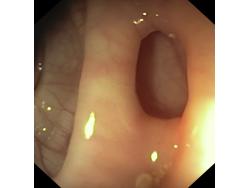

Uchyłki